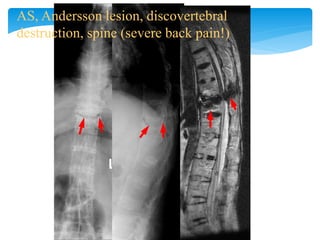

AS, Andersson lesion, discovertebral

destruction, spine (severe back pain!)

Spine

T1 white, STIR dark

Bone marrow

edema, STIR white,

T1 dark

Romanus lesion

Active lesion

Chronic lesion